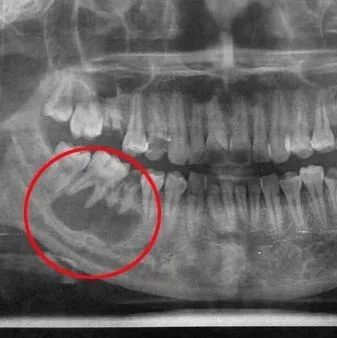

遇到长了颌骨囊肿的患者怎么办?是大手术吗?

颌骨囊肿是指在颌骨内出现一含有液体的囊性肿物,逐步增大、颌骨膨胀破坏,据其发病原因可分为牙源性及非牙源性两大类,牙源性者即囊肿由成牙组织或牙演变而来;非牙源性囊肿则可由胚胎发育过程中残留于颌骨内的上皮...